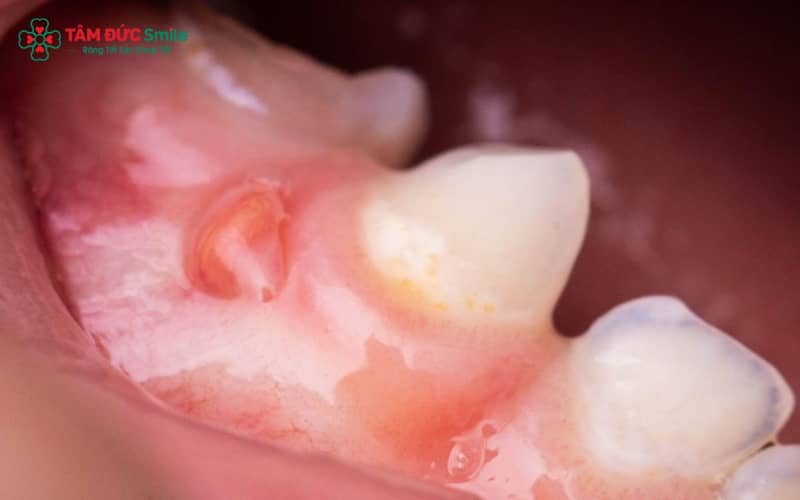

1.4. Có mủ hoặc tụ dịch quanh chân răng

Một số trường hợp xuất hiện tụ mủ chân răng hoặc dịch trắng đục quanh vùng sưng. Đây là biểu hiện của áp xe răng, tình trạng nhiễm trùng nặng nếu không xử lý kịp thời có thể dẫn đến răng lung lay hoặc tiêu xương hàm.

2.3. Áp xe chân răng gây tụ mủ, sưng tấy

Áp xe chân răng hình thành khi vi khuẩn xâm nhập vào phần chân răng hoặc vùng nha chu, tạo ổ mủ. Người bệnh sẽ thấy tụ dịch quanh chân răng, sưng đỏ và đau nhói. Nếu không điều trị sớm, vi khuẩn có thể lây lan ra các vùng mô mềm xung quanh.